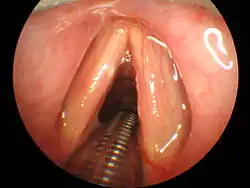

Unlike basic airway management, such as the head tilt/chin lift or jaw-thrust maneuver, advanced airway management relies on the use of medical equipment and advanced training in anesthesiology, emergency medicine, or critical care medicine. Certain invasive airway management techniques can be performed with visualization of the glottis or "blind" – without direct visualization of the glottis. Visualization of the glottis can be accomplished either directly by using a laryngoscope blade or by utilizing newer video technology options.

Tracheal intubation, often simply referred to as intubation, is the placement of a flexible plastic or rubber endotracheal tube (ETT) into the trachea to maintain an open airway, allow for effective ventilation, protect the airway from aspiration (when a cuffed ETT is used), and to serve as a conduit through which to administer inhaled anesthetics. It is frequently performed in surgery, critically injured, ill or anesthetized patients to facilitate ventilation of the lungs, including mechanical ventilation, and to prevent the possibility of asphyxiation or airway obstruction. The most widely used route is orotracheal intubation, in which an endotracheal tube is passed through the mouth, through the vocal cords, and into the trachea. In a nasotracheal intubation, a nasotracheal tube (NTT) is passed through the nose, through the vocal cords, and into the trachea.[6][7][8]

Direct Laryngoscopy

Classically, tracheal intubation has been performed utilizing direct laryngoscopy to obtain direct visualization of the vocal cords. There are multiple different laryngoscope blade styles, shapes, and lengths from which to choose based on patient anatomy and clinician preference.[9] In North America, the Macintosh blade is the most commonly used curved blade while the Miller blade is the most common straight blade.[9] Many modern laryngoscopes are equipped with a fiberoptic light source to aid in visualization. Regardless of blade shape, direct laryngoscopy technique involves passage of the laryngoscope through the mouth and into the back of the throat. Manipulation of the neck and lifting of the tongue allows for direct visualization of the larynx and vocal cords by the operator. Following visualization, the endotracheal tube can be passed along the blade, through the vocal cords, and into the trachea.[10]

Video Laryngoscopy

Multiple intubation tools are now available with built-in video technology, also known as video laryngoscopy.[9] The GlideScope model utilizes a curved laryngoscopic blade with an integrated camera connected to a large external monitor. The McGrath model has a compact design with a small display directly attached to the laryngoscopic blade. The operator introduces the video laryngoscope through the mouth with a technique similar to direct laryngoscopy. The larynx and vocal cords are visualized via the camera and the operator is able to pass the endotracheal tube through the vocal cords and into the trachea under direct visualization on the video monitor.[9] Studies have shown that when compared to direct laryngoscopy, video laryngoscopy resulted in fewer failed intubation attempts, especially in patients with known difficult airways.[11] Limitations of video laryngoscopy exist and prevent the exclusive use of this method over direct laryngoscopy. Excessive blood and saliva in the airway can cover the camera lens on the video laryngoscope and obscure effective visualization of the anatomy, preventing effective intubation attempts. This is of importance in patients with trauma to their airway, increasing the amount of blood present, and patients taking sialogogues, or drugs that increase the flow of saliva.[12]

Fiberoptic Intubation

In patients with known difficult airways, fiberoptic intubation can be considered. This technique involves the use of a flexible fiberoptic bronchoscope for visualization of the vocal cords. The bronchoscope can be passed directly into the trachea and the endotracheal tube can be threaded over the bronchoscope into position. This technique has various advantages over direct laryngoscopy and video laryngoscopy techniques. The fiberoptic scope is flexible and can be directed by the operator, allowing it to traverse the upper airway with minimal manipulation of the patient's neck. The operator can manipulate the device around obstructions in the upper airway, making the technique advantageous for patients with cancer or swelling in the upper airway. The device is relatively small compared to a laryngoscope and can therefore be implemented in patients with small mouth openings. Additionally, the fiberoptic scope can be passed through the nostril to provide visualization for a nasotracheal intubation. Lastly, fiberoptic intubation can be conducted in an awake patient with sufficient use of local anesthetics, which can prove useful in patients who would otherwise be unable to be anesthetized without having a secure airway in place beforehand. [9]